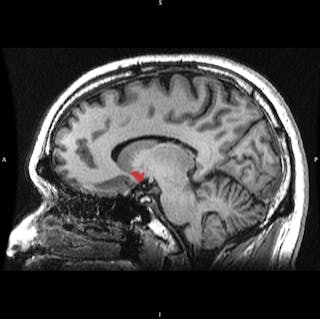

薬物は、食物、水、性など、他の報酬と同じ脳回路に作用します。 報酬に遭遇すると、神経細胞の集団が、脳の報酬回路の一部である側坐核などの部位に神経伝達物質であるドーパミンを放出します。 ドーパミンは、注意と行動を喚起する働きをします。 何か重要なことが今起こりましたよ」と教えてくれるのです。 その近くにいて、どうすればまた起こるかを学ぶために注意を払いなさい “と。

ドーパミンスパイクは、それを引き起こした出来事を魅力的に見せます。 コカインのような薬物が、吸引ではなく、喫煙や注射によって急速に脳に到達すると、側坐核のドーパミンレベルがより速く上昇するのです。